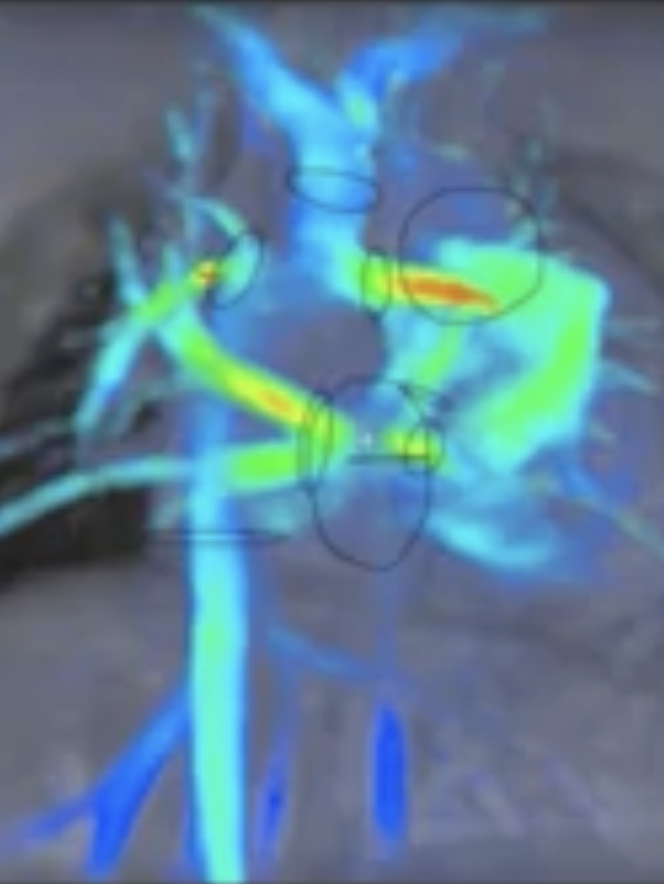

Det är en stor studie där barnen genomgår flera olika undersökningar under tre dagar. Det handlar bland annat om arbetsprov med gasanalys, hjärtultraljud, lungfunktionsundersökningar, MR av hjärta och lever, samt undersökningar av lymfsystem och blodkärl.

Barn med enkammarcirkulation har lägre maximal syreupptagningsförmåga än friska jämnåriga, vilket man också har sett tidigare. Men forskarna har nu också kunnat visa att barn som har mer kollateralflöde, alltså blod som går andra vägar än genom lungorna, ofta har sämre kondition och lägre syreupptag.

De har också sett att barn med enkammarcirkulation verkar ha sämre förmåga att anpassa lungblodflödet när det venösa återflödet ökar. Det kan vara en viktig pusselbit för att förstå varför många blir trötta lättare eller har sämre ork.